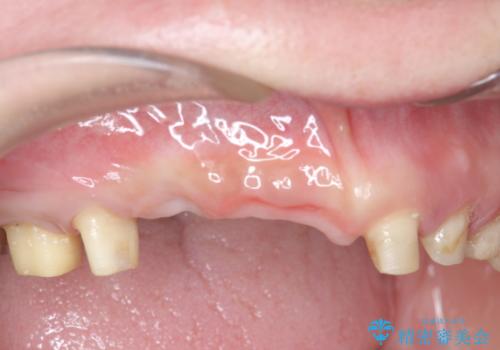

咬合性外傷による歯槽骨吸収 ブリッジ補綴

- 歯が揺れしっかりとものが噛めないことの改善を求めて来院されました。

保存の難しい歯の抜歯、保存できる歯の歯周病治療、欠損部位の歯槽堤形態回復を含めブリッジによる安定した咬合機能回復を計画します。